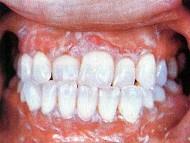

问题 引起牙龈剥脱的最常见的疾病是 ( )

选项 A.B族维生素缺乏 B.维生素A缺乏 C.维生素C缺乏 D.特异性脱骨性龈炎 E.类天疱疹及扁平苔藓

答案 E